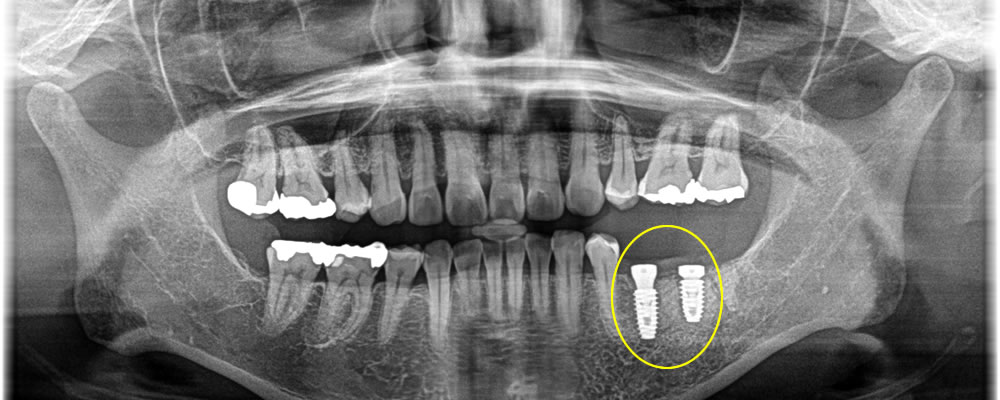

大臼歯2本分欠損していたため、しっかりと噛み合うよう、インプラントも2本埋入しました。

埋入したインプラントと顎骨がしっかりと結合した後、上部構造を製作・装着して治療完了となりました。治療後は、もともとあった歯と同じように違和感なく噛めるようになり、大変満足していただいております。